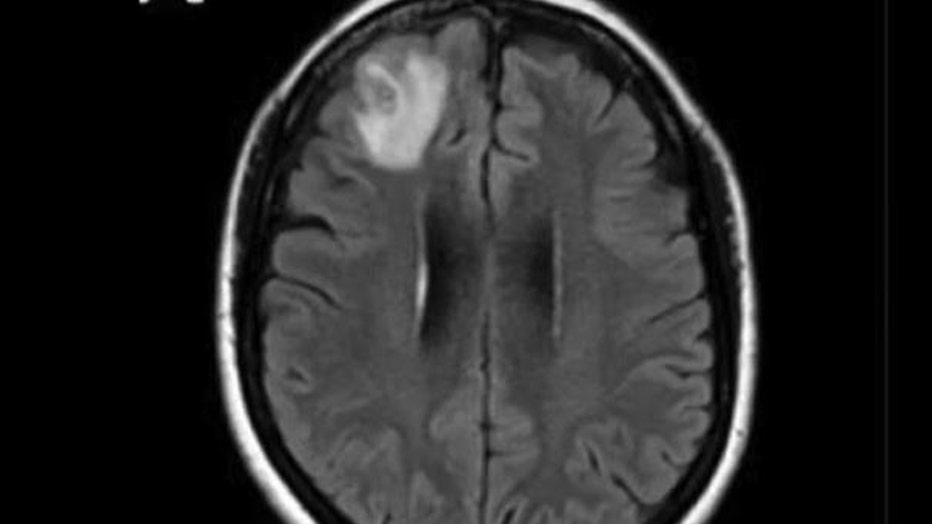

The woman had been admitted to the hospital after experiencing forgetfulness and worsening depression over three months. Scans showed changes in her brain.

"This patient had been treated ... for what was a mystery illness that we thought ultimately was a immunological condition because we hadn’t been able to find a parasite before and then out of nowhere, this big lump appeared in the frontal part of her brain," Senanayake said.